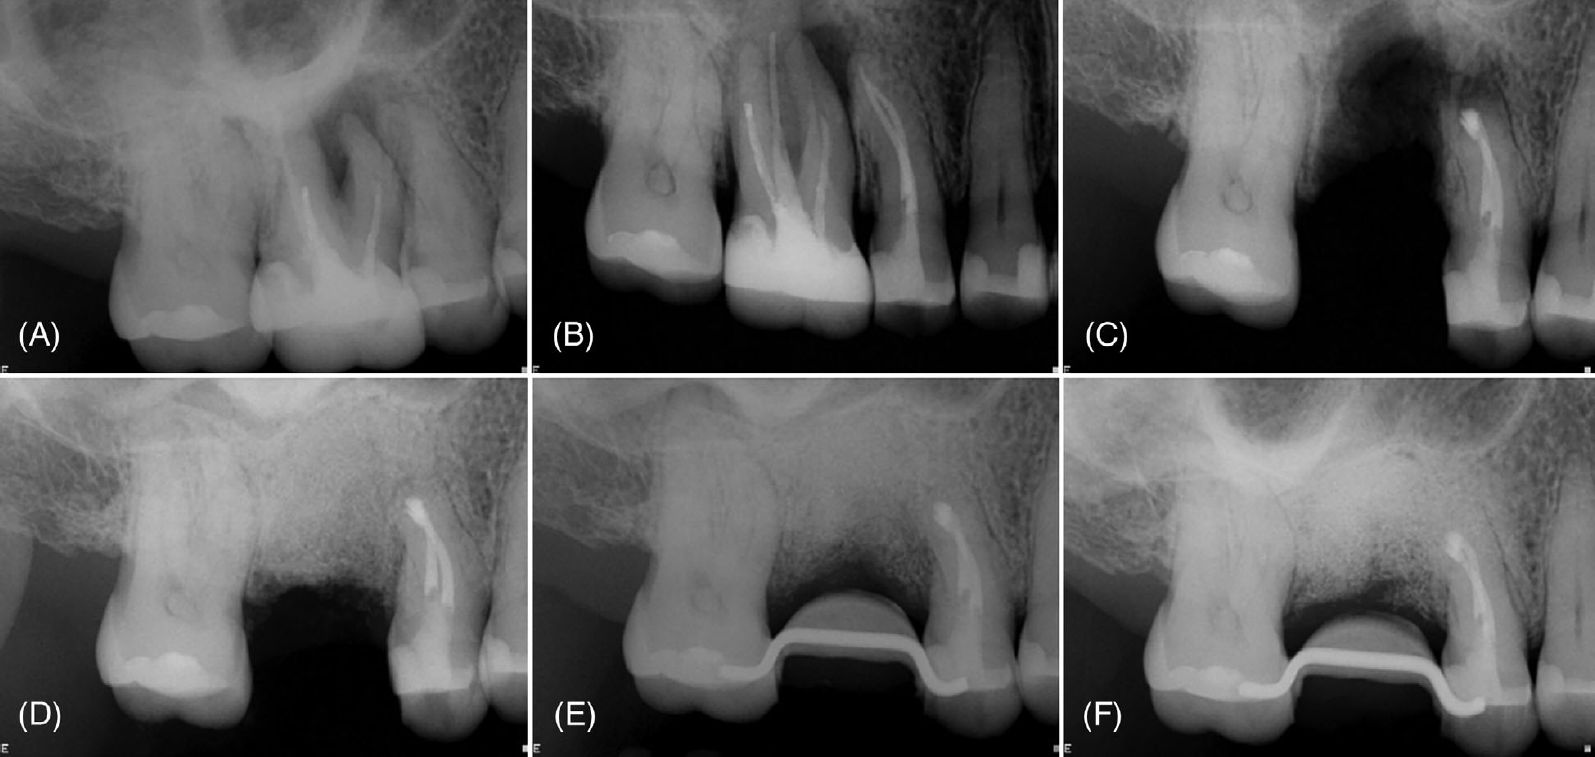

Фото 4. (A) Периапикальная рентгенограмма, демонстрирующая поражение, вовлекающее зубы 16 и 15. (B) Периапикальная рентгенограмма после эндодонтического лечения зуба 15. (C) Интраоперационная рентгенограмма после удаления зуба 16 и ретроградного пломбирования зуба 15. (D) Непосредственная послеоперационная рентгенограмма после направленной костной регенерации. (E) Рентгенограмма через 1 месяц наблюдения, выполненная после установки временной реставрации зуба 17. (F) Рентгенограмма через 8 месяцев наблюдения

Фото 7. (A) Периапикальная рентгенограмма с рентгенопрозрачным очагом в периапикальной области зубов 18 и 17, кариес, дефектные реставрации и неудовлетворительное эндодонтическое лечение. (B) Периапикальная рентгенограмма после эндодонтического перелечивания зуба 18. (C) Интраоперационная рентгенограмма после удаления зуба 17, кюретажа альвеолы и апикопластики зуба 18. (D) Непосредственная послеоперационная рентгенограмма после костной регенерации и синус-лифтинга. Рентгенограммы через 1 месяц (E) и 3 месяца (F) наблюдения